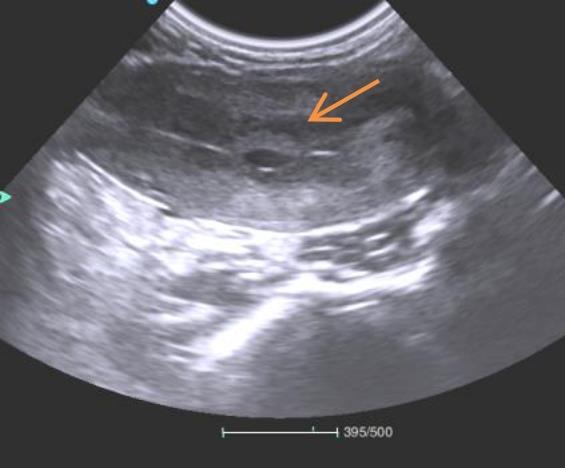

图2 妊娠初期雌猴孕囊B超切面

注:图中箭头所指区域可见成型的孕囊结构。

Figure 2 Ultrasound cross-sectional view of gestational sac in a female monkey during early pregnancy

Note:The area indicated by the arrow in the figure shows a well-formed gestational sac structure.